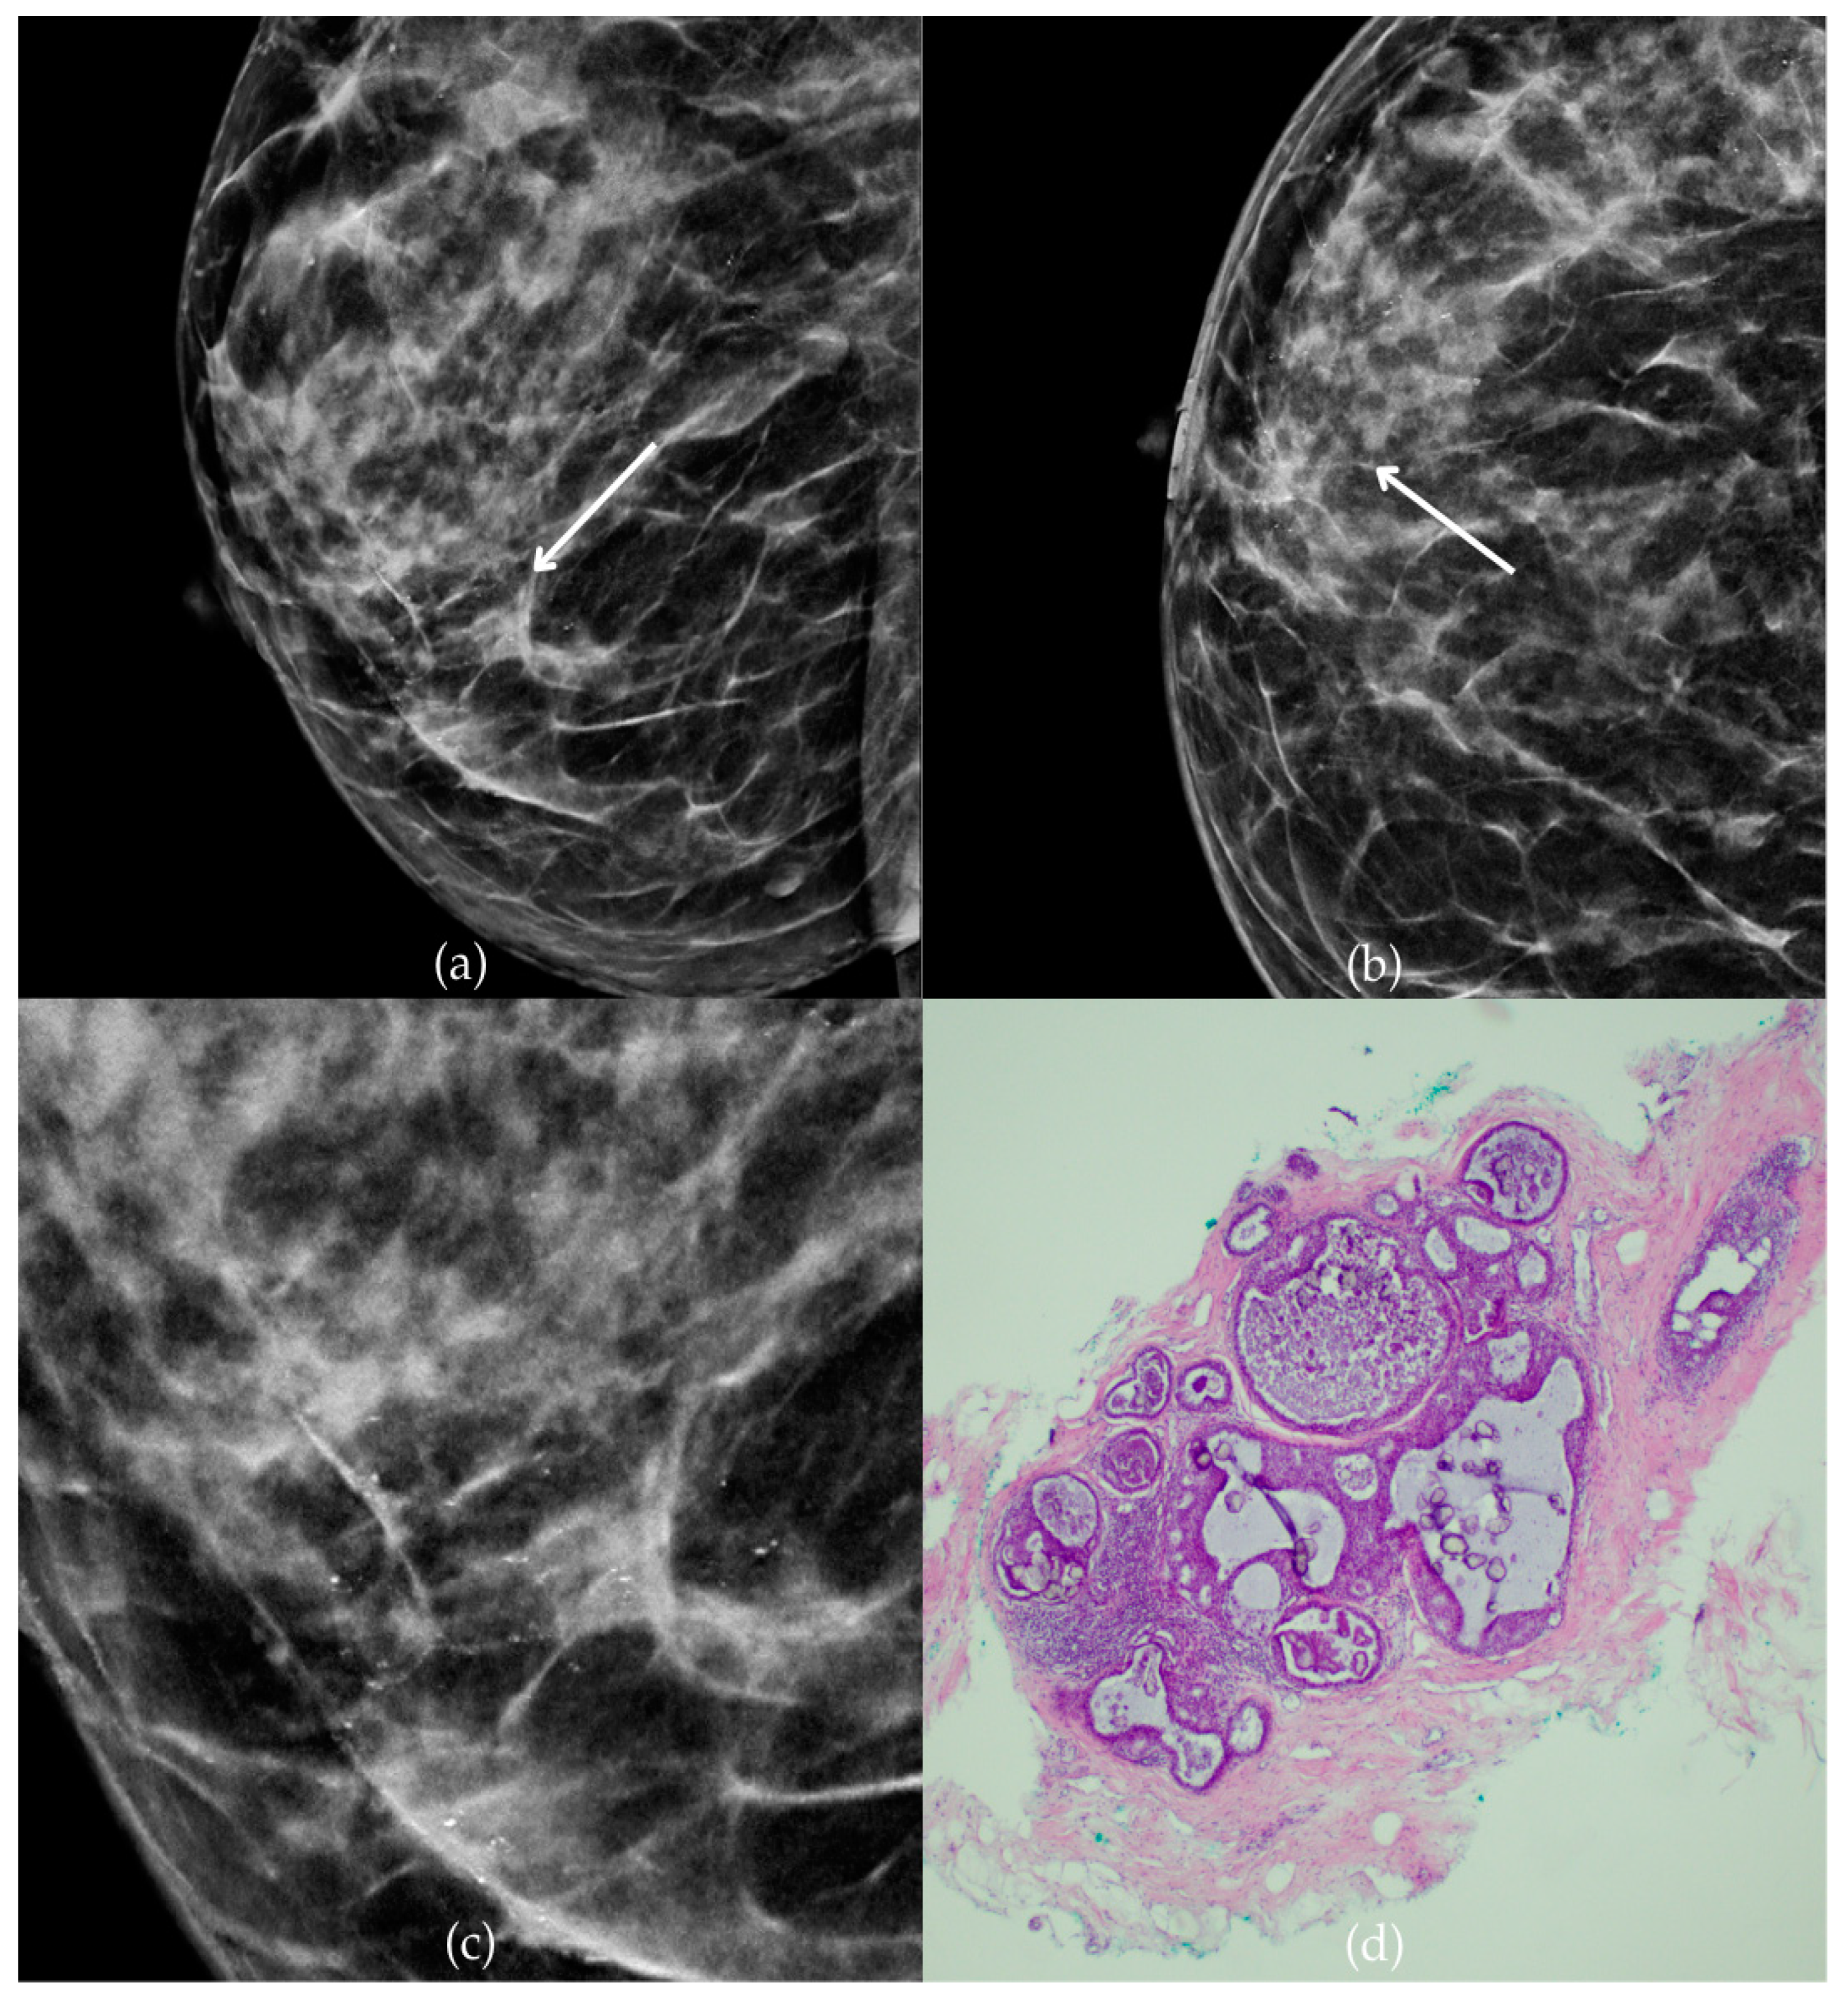

Figure 1 presents mammographic and histopathological images of a 74-year-old patient. The mammogram of the right breast shows grouped coarse heterogeneous and fine pleomorphic calcifications in the upper outer quadrant, classified as a BI-RADS 4 finding. Given the suspicious nature of these findings, a biopsy was performed. A tissue analysis confirmed the presence of a DCIS (category B5a). The patient underwent quadrantectomy, and the postoperative pathology confirmed the diagnosis. At the most recent follow-up, conducted one year after the initial diagnosis, the US examination was classified as BI-RADS 2, indicating benign findings.

Figure 1.

Ductal carcinoma in situ (DCIS). (a) Mediolateral oblique (MLO) mammography view; (b) craniocaudal (CC) mammography view of the right breast showing grouped coarse heterogeneous and fine pleomorphic calcifications (marked with arrows) in the upper outer quadrant. (c) Magnified mammographic image of grouped coarse heterogeneous and fine pleomorphic calcifications. (d) The histopathological image of the biopsy sample reveals the characteristic features of DCIS (HE staining; 40× magnification).